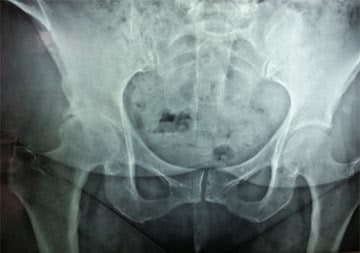

Osteoartritis

Es el desgaste de las articulaciones producto del envejecimiento y de algunos factores aceleradores como las enfermedades, los accidentes o los riesgos laborales. Puede presentarse en todas las articulaciones incluyendo las de la columna, en las que se denominan espondiloartrosis.